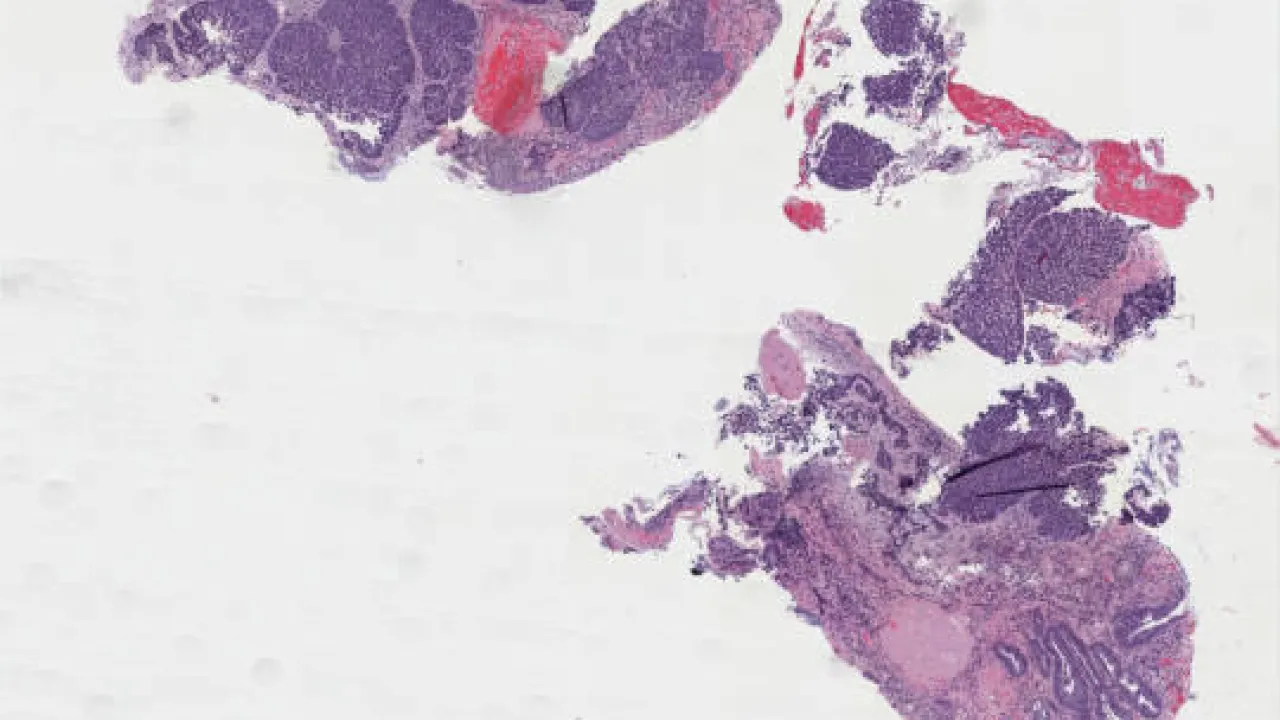

Pancreas, Solid pseudopapillary tumor